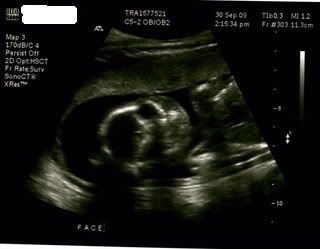

Ultrasound pictures 19weeks, 1 day (measured at 19weeks, 4 days - not too shabby for just relying on charting for my date).

creepy face picture: